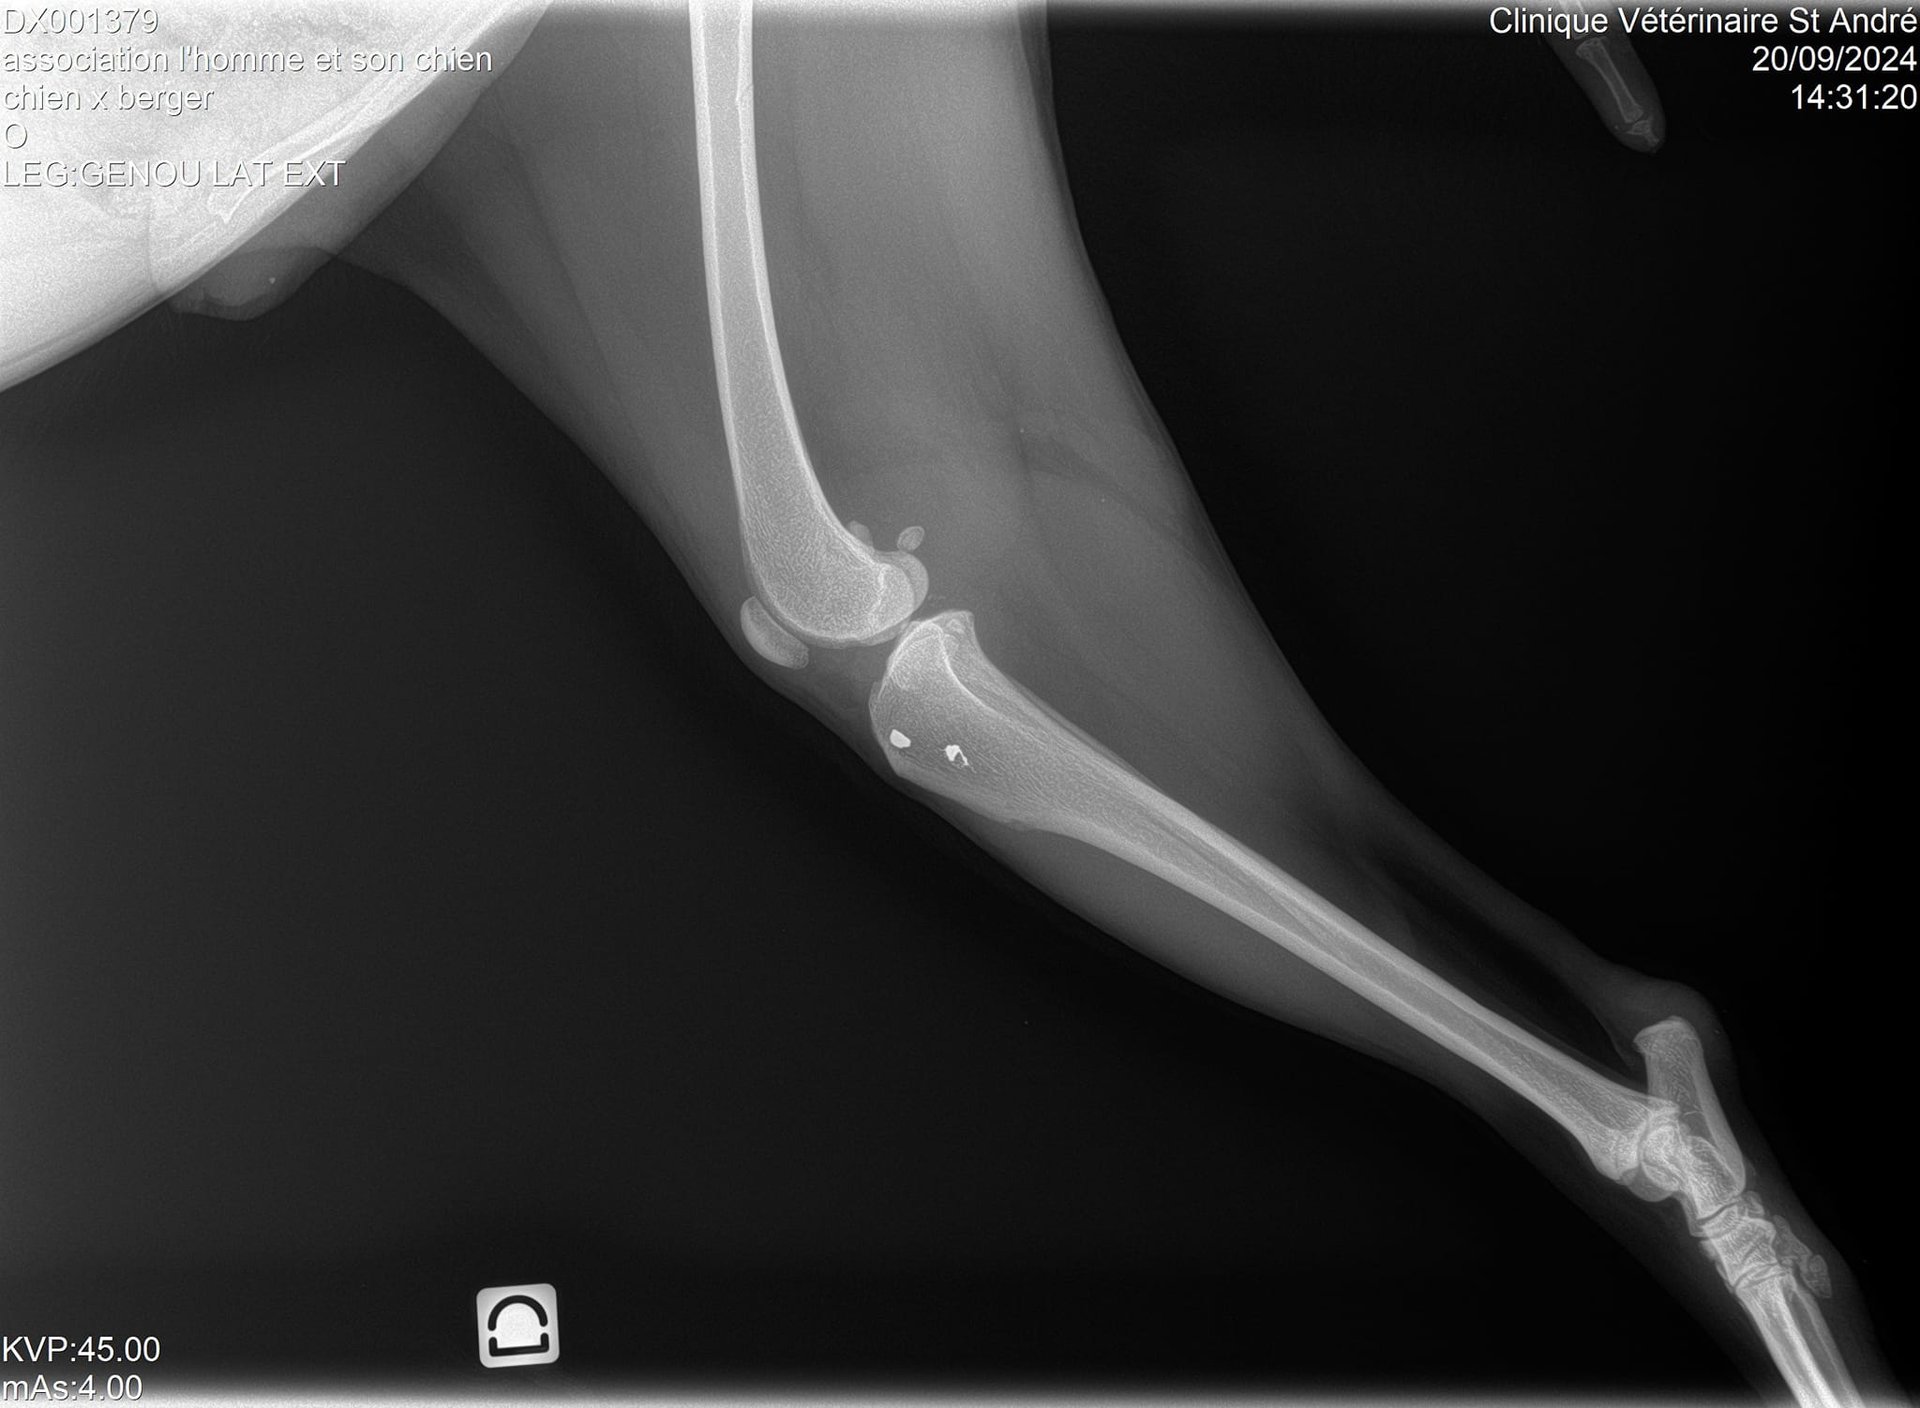

Sa patte avant gauche, criblée de balles, est détruite et, malgré ça, il est obligé de s'en servir car il ne pose pas toujours sa patte arrière droite…

Vous allez halluciner en voyant ses radios !